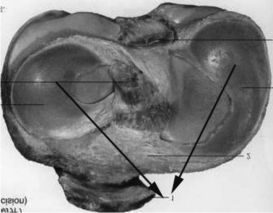

②学习关节内软骨,向学生展示关节内软骨的图片,指出人体内存在的两种类型关节内软骨,并指出各自的分布典型位置,要求学生思考关节内软骨有哪些作用,结合上肢下肢活动的特点指出两类软骨作用的差异性。(学生集体回答)

图4-5-10 腕关节辅助结构——关节盘

图4-5-11 膝关节辅助结构——半月板